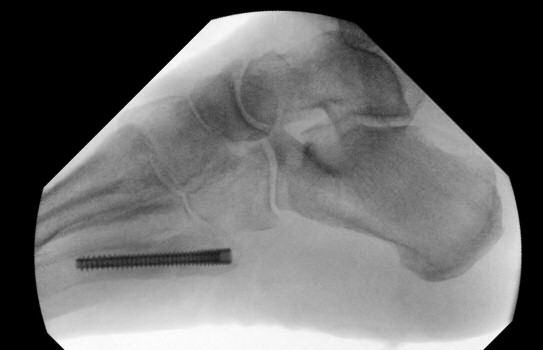

Mellan de röda strecken: ungefärligt läge för Jones-fraktur. Längre proximalt: avulsionsfraktur.

Exempel på Jones-frakturer, första bilden färsk, andra bilden ej läkt, tredje bilden efter operation.